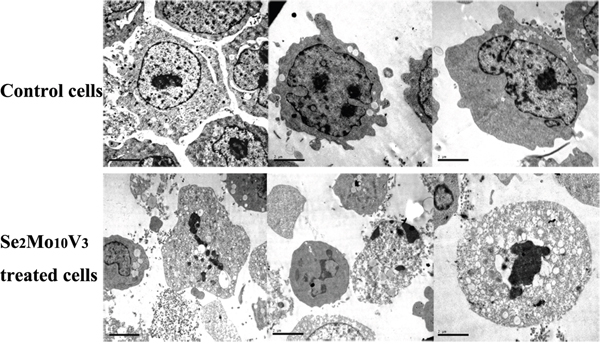

Figure 2: 50 mg/L Se2Mo10V3 induced apoptosis in K562 cells in a TEM expreiment. Scale = 2.00 μm. Data are representative of three independent experiments.

Se2Mo10V3 induced apoptotic morphology in K562 cells

As shown in Figure 3, typical indicators of apoptosis, such as chromatin fragmentation, condensation and margination, cytoplasm vacuoles, and disappearance of cytolemma microvilli, were observed to a greater extent in K562 cells treated with 50 mg/L Se2Mo10V3 than in control cells, which were characterized by normal chromatin, uniform cytoplasm, the presence of cytolemma microvilli, and diastolic cell bodies.

Transmission electron microscopy (TEM)

K562 cell morphology was examined using TEM. Cells were treated with 50 mg/L Se2Mo10V3 for 24 h. Cell precipitates were then fixed with glutaraldehyde, post- fixed with osmium tetroxide, dehydrated with a graded alcohol series, immersed in epoxy resin and acetone, and embedded in epoxy resin. Ultra-thin sections were then prepared, dyed using uranyl acetate and lead citrate, and examined with a JEM-100 CX-II TEM (Jeol).